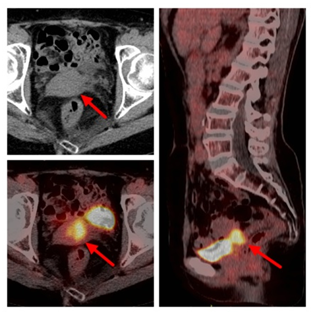

进行PET/CT检查后,医生通过PET图像、CT图像、PET/CT融合图像的阅片,胸骨呈术后改变,术区未见明显病变及显像剂的异常摄取,未见复发或残留(图2);右肺野近胸膜下可见多个边缘模糊的小结节,与前次CT片比较病变缩小,没有显像剂的异常摄取,符合良性病变。同时,发现宫颈处有斑片状的异常显像剂摄取,密度没有异常,考虑占位性病变(图3)。诊断医生再次询问李阿姨及家属,患者于48岁停经,目前没有异常引道流血等妇科症状,建议进行妇科检查。之后完成盆腔磁共振检查及宫颈活检,病理诊断为宫颈鳞状细胞癌,临床分期为IIA2期,经院内多学科会诊,依据诊疗规范,首选同步放化疗+阴道后装放疗的治疗策略。通过PET/CT检查,发现了胸腺瘤之外的第二原发恶性肿瘤,体现了PET/CT检查的高敏感性、高准确性,为临床更好地采取规范诊疗措施提供依据。

图3:红箭:宫颈处明显高代谢占位,“点亮”病灶